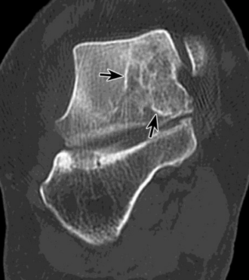

| What type of fracture is this? | Osteochondral fracture |

| What type of fracture is this? | Impaction fraction |

| What type of fracture is this? | Intra-articular fracture |